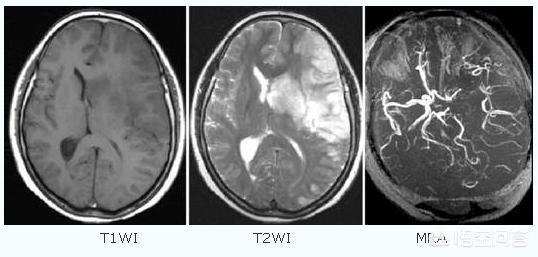

Son mari l'a emmené à l'hôpital, où une série d'examens d'imagerie ont été effectués et le diagnostic a été celui d'un infarctus cérébral. Le médecin a recommandé de procéder à un examen d'imagerie et d'enlever le caillot si nécessaire, ainsi que d'utiliser des médicaments pour contrôler les symptômes.

De nombreux ruraux ne reconnaissent pas l'infarctus cérébral. Qu'est-ce que l'infarctus cérébral ? L'infarctus cérébral est une maladie dans laquelle divers emboles sanguins (par exemple, un thrombus fixé à la paroi du cœur, une plaque d'athérosclérose, de la graisse, des cellules tumorales, du fibro-cartilage ou de l'air, etc.) pénètrent dans les artères cérébrales avec le flux sanguin et obstruent les vaisseaux sanguins, provoquant une nécrose ischémique des tissus cérébraux dans la zone desservie par les artères.

Pour simplifier, il s'agit de la nécrose des cellules cérébrales qui se produit lorsque les vaisseaux sanguins du cerveau sont bloqués, provoquant une ischémie cérébrale.

- Les AVC se divisent en AVC hémorragiques et en AVCaccident vasculaire cérébral ischémiqueIl existe deux catégories : la première est généralement appelée "hémorragie cérébrale" ou "hémorragie cérébrale", qui se manifeste généralement par des maux de tête intenses, des vomissements, voire le coma et d'autres symptômes ; la seconde est appelée "hémorragie cérébrale" ou "hémorragie cérébrale".La maladie de l'infarctus cérébral se réfère en fait à cette dernière。

- Infarctus cérébralÉgalement appelée "infarctus cérébral", "thrombose cérébrale" ou "embolie cérébrale", elle se manifeste généralement par l'apparition soudaine d'une faiblesse ou d'un engourdissement d'un côté des membres, d'un engourdissement d'un côté du visage ou d'une déformation des coins de la bouche, et d'un manque de réactivité, une perte d'équilibre, des difficultés à avaler, des difficultés à parler, des troubles de la conscience ou des convulsions.

L'infarctus cérébral, également connu sous le nom clinique d'accident vasculaire cérébral ischémique, est un problème d'approvisionnement en sang des vaisseaux sanguins du cerveau causé par un certain nombre de raisons telles que l'athérosclérose, l'hypertension, le diabète sucré et les maladies coronariennes, entraînant une ischémie, une hypoxie et une nécrose des tissus cérébraux locaux.